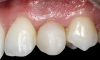

To demonstrate the principles and protocols described in this article, three case examples are included. The first case involves the treatment of a patient who sought replacement of the maxillary left canine (tooth No. 11) with an implant-supported restoration (Figure 11 through Figure 34), and in the second case, the patient presented for replacement of the maxillary left central incisor (tooth No. 9) (Figure 35 through Figure 44). In the third case, the patient also presented for replacement of the maxillary left central incisor (tooth No. 9) but had a preexisting bonded pontic made from the natural tooth. This was utilized in lieu of a composite tooth shell to fabricate the immediate provisional restoration. (Figure 45 through Figure 57).

(45.) A patient presented for the replacement of the maxillary left central incisor with a bonded pontic made from the natural tooth, which was removed.

Figure 45